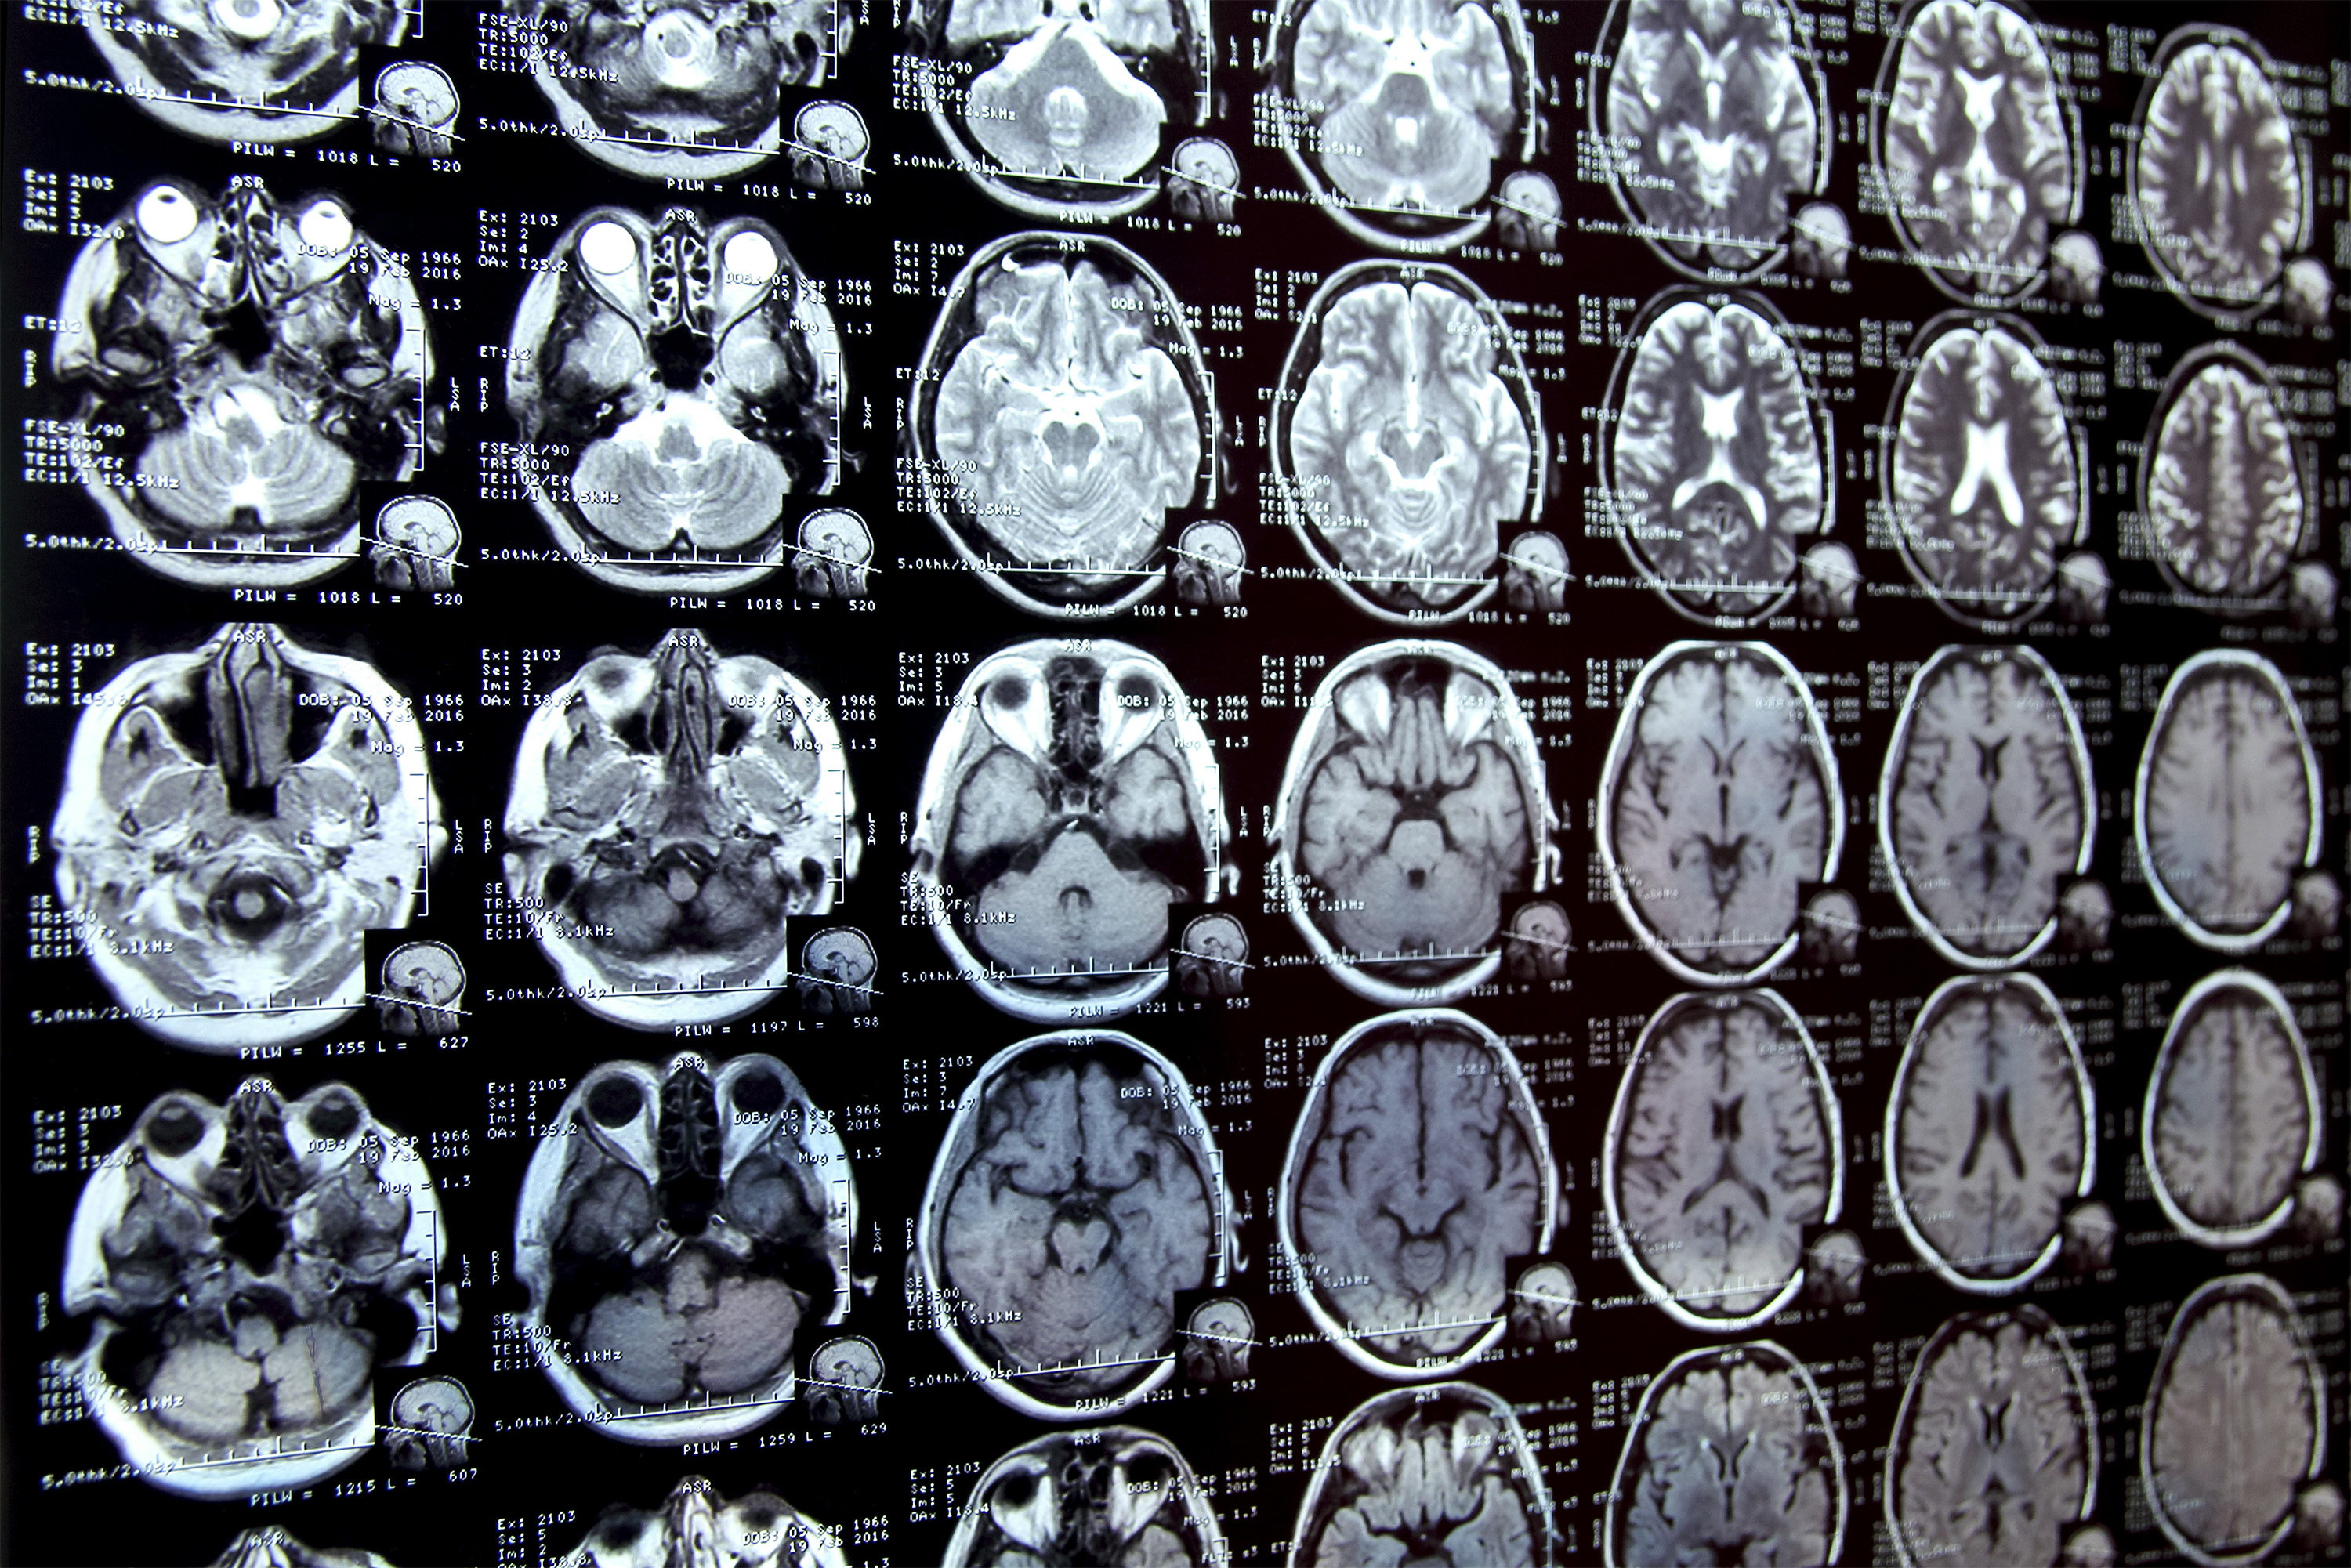

Annotating regions of interest in medical images, a process known as segmentation, is often one of the first steps clinical researchers take when running a new study involving biomedical images.

For instance, to determine how the size of the brain’s hippocampus changes as patients age, the scientist first outlines each hippocampus in a series of brain scans. For many structures and image types, this is often a manual process that can be extremely time-consuming, especially if the regions being studied are challenging to delineate.